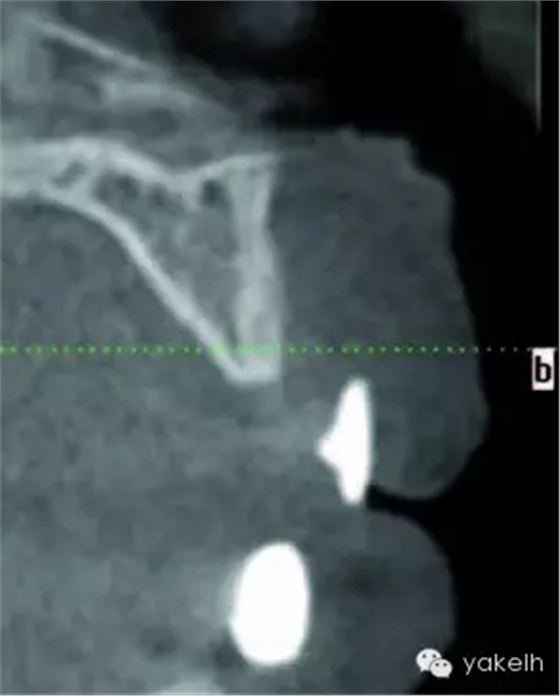

¤¤全景片以及根尖片可用于評(píng)估骨缺損、周圍的牙列以及局部解剖形態(tài)。計(jì)算機(jī)斷層攝影(CT)對(duì)骨缺損的三維觀察十分有用,也能用于評(píng)估口內(nèi)供骨區(qū)的情況??山Y(jié)合使用種植設(shè)計(jì)軟件與CT掃描,更加精確地評(píng)估患者所需重建的骨量。使用計(jì)算機(jī)掃描制備頜骨的立體光刻模型,以制訂進(jìn)一步計(jì)劃。臨床醫(yī)生通過對(duì)架研究模型及診斷蠟型的研究分析,來把握牙槽嵴形態(tài)與預(yù)期修復(fù)結(jié)果的關(guān)系[7]。它們也可用于CT掃描中X線模板的制備[8]。該模板阻射影的輪廓,提示了修復(fù)體在殘余牙槽嵴斷層掃描的位置(圖13.1,圖13.2)。這有助于決定所需移植骨的大小以及取骨的部位。在骨移植手術(shù)中,設(shè)計(jì)預(yù)期修復(fù)體位置的模板,對(duì)于移植物植入位置的確定以及完成骨移植的要求也是很有用的。

圖13.2 X線模板的CT掃描,模板輪廓提示了預(yù)期修復(fù)體位置與殘余牙槽嵴的位置關(guān)系。